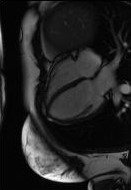

Shape instantiation which predicts the 3D shape of a dynamic target from one or more 2D images is important for real-time intra-operative navigation. Previously, a general shape instantiation framework was proposed with manual image segmentation to generate a 2D Statistical Shape Model (SSM) and with Kernel Partial Least Square Regression (KPLSR) to learn the relationship between the 2D and 3D SSM for 3D shape prediction. In this paper, the two-stage shape instantiation is improved to be one-stage. PointOutNet with 19 convolutional layers and three fully-connected layers is used as the network structure and Chamfer distance is used as the loss function to predict the 3D target point cloud from a single 2D image. With the proposed one-stage shape instantiation algorithm, a spontaneous image-to-point cloud training and inference can be achieved. A dataset from 27 Right Ventricle (RV) subjects, indicating 609 experiments, were used to validate the proposed one-stage shape instantiation algorithm. An average point cloud-to-point cloud (PC-to-PC) error of 1.72mm has been achieved, which is comparable to the PLSR-based (1.42mm) and KPLSR-based (1.31mm) two-stage shape instantiation algorithm.